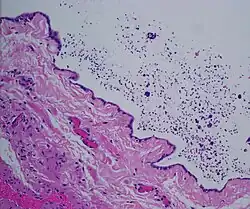

Micrograph of a spermatocele. The characteristic sperm are present (black dots - left of image). H&E stain. -

Dilated rete testis containing spermatozoa within cyst lumen. H&E stain 20x